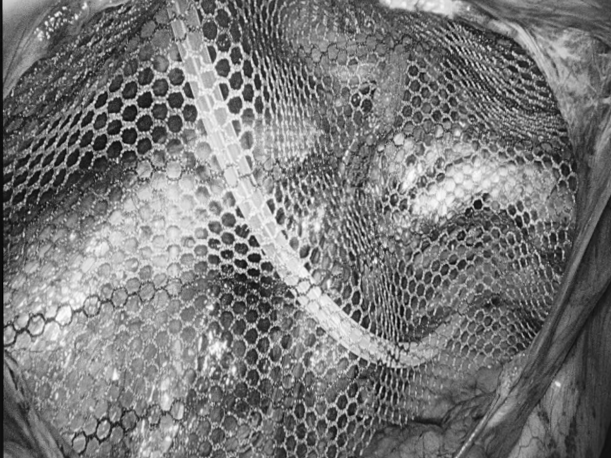

您是否正在经历 肛周肿痛、瘙痒的困扰? 是否发现过便血 或是有小肉球脱出来? 是不是因为觉得尴尬 所以一直拖着没去看? …… 这些难言之隐的背后 往往是痔疮、肛裂等 肛周疾病的信号 这些常见问题,往往与我们的日常生活习惯息息相关:长时间坐着不动、如厕时久蹲、饮食中缺乏蔬菜水果都可能增加患病风险。预防的关键在于主动调整: ✔饮食要“润”:多吃蔬菜、水果、粗粮,保证饮水,让大便保持通畅松软。 ✔久坐要“动”:每隔一小时起身活动几分钟,减轻肛周压力。 ✔如厕要“快”:减少如厕时间,避免久蹲和过度用力。 ✔清洁要“轻”:便后保持清洁,用温水冲洗或柔软纸巾轻拭。 养成良好的生活习惯,是守护肛周健康的第一道防线。 目前,治疗这类疾病的方法有很多。在贵州航天医院普外科,我们在常规诊疗基础上,进一步融入了中医调理的优势,为您提供一种更注重恢复过程中的舒适度、也更关注身体的整体调理特色方案——中西医结合治疗肛周疾病,希望能帮助您更安心、更顺畅地解决难言之隐。 【中西医结合,优势互补】 ※西医精准明确,技术微创:借助电子肛肠镜等设备清晰诊断,并运用PPH(吻合器痔上黏膜环切术)、TST(选择性痔上黏膜吻合术)等微创手术技术,精准处理病灶,创伤小、出血少。 ※中医整体调理,促进康复:通过内服外用中药,协助术后消肿止痛、促进创面愈合,并帮助调整内在体质,减少复发。 【中西医结合诊疗的优势】 ▶术前可中医干预:对处于急性炎症期的患者,先行中药坐浴、外敷等缓解肿痛,创造更好手术条件,部分患者可能因此免于手术。 ▶术中微创精准:由经验丰富的肛肠外科医生操作,注重保护正常功能组织。 ▶术后康复加速: •中药内服调理:根据个人体质开具药方,促进恢复。 •中药坐浴外治:使用科室配置的洗剂,帮助保持清洁、缓解疼痛、舒适伤口。 •专业西医护理:配合规范的伤口换药与护理,保障愈合过程顺利。 •多模式镇痛:采用中西药结合的多种镇痛方式(如口服、外用、中药制剂等),有效缓解术后疼痛,帮助您更舒适、安心地度过恢复期。 适合以下常见肛周疾病患者: 各期痔疮(内痔、外痔、混合痔)、肛裂、肛周脓肿、肛瘘、直肠息肉、肛周湿疹、肛门尖锐湿疣、肛乳头瘤、肛门狭窄、肛门失禁等。 温馨提示: 1.肛周疾病重在早发现、早干预,请不要因羞涩而延误最佳治疗时机。 2.本文仅为疾病科普与诊疗介绍,不能替代任何专业的医疗建议,如有任何健康问题,请务必及时咨询并遵从专业医生的诊疗意见。 注:部分图片来源于网络,如有侵权,请联系删除。 贵州航天医院普外科专家简介 高大勇 普外科(肛肠外科)学科带头人、名誉主任,主任医师、教授 临床擅长:对中西医结合诊治肛肠学科各种常见病、多发病及疑难杂症等具有丰富的临床经验。 原遵义市第一人民医院(遵义医科大学第三附属医院)、遵义市中医院肛肠科主任。中华中医药学会肛肠分会常委,全国中医肛肠学科名专家,中国健康促进与教育协会肛肠分会常委,中国康复医学会肛肠疾病康复专业委员会常委,中国民间中医医药研究开发协会肛肠分会副秘书长,中国医师协会中西医结合肛肠医师专业委员会常委,国家二级心理咨询师,贵州省第一批中医名医工作指导老师,遵义市名中医,遵义市肛肠学会会长,遵义市肛肠质控中心名誉主任,遵义市中西医结合学会名誉会长,遵义市健康科普专家,原贵州省中西医结合学会肛肠分会副主任委员、贵州省中医肛肠质控中心副主任、遵义市医学会医疗鉴定委员会专家、遵义市卫生系列高评委。发表论文30余篇,主编和参编医学著作5本,主持省级科研课题2项、市级科研课题2项、院级科研课题1项。 梁 跃 普外科党支部书记、主任,主任医师 临床擅长:对普外科各类肿瘤手术具有丰富的临床经验。 毕业于遵义医学院,遵义市医学会小儿外科学分会常务委员,遵义市肛肠协会理事,遵义市医学会核医学分会(第二届)委员会委员;荣获第三期“黔医人才计划”优秀学员称号;主持市级课题1项,完成省级课题1项,在国内各类刊物上发表论文10余篇。 钱科洪 民盟盟员,普外科副主任医师 临床擅长:从事普外科临床工作30余年,对各类普外科疾病的诊治、乳腺、甲状腺、胃十二指肠、结直肠等疾病及疑难杂症具有丰富的临床经验。 毕业于遵义医学院临床医疗系,2009年前往中山大学附属第一医院微创外科进修学习,在国内各专业期刊发表论文数篇。 贵州航天医院普外科简介 基本情况 贵州航天医院普外科成立于1968年,前身属于航天部O61基地3417医院外一科,1998年3417医院、3427医院合并后更名为普外科,下设胃肠外科、肛肠外科2个亚专业科室,拥有在全市较为先进的专科设备和技术,是中国疝病专科联盟单位,贵州医科大学附属医院胃肠外科专科联盟单位。开放床位40张,配备医护人员21人。 专科特色 普外科致力于胃肠及肛肠疾病的外科临床诊治及科研,以腹腔镜微创外科技术为本,形成以快速康复治疗胃肿瘤、结直肠肿瘤、小肠肿瘤、直肠脱垂、肥胖病、急腹症、各类疝、痔、瘘等专科特色,同时注重胃肠疾病尤其是结直肠恶性肿瘤的基础研究和临床转化研究,总体诊断和治疗水平在区域同级医院居于领先水平。 开展手术:腹腔镜下胃癌根治术,腹腔镜下袖状胃切除术,腹腔镜下胃肠道间质瘤切除术,腹腔镜下结、直肠癌根治术,胃癌、结直肠癌的精准治疗,腹腔镜下小儿疝气、成人疝修补术,腹腔镜下阑尾手术,内痔的硬化注射治疗及痔疮的微创治疗:ATH、PPH、TST,直肠脱垂的各种手术治疗,难治性伤口VSD技术,鼻胃肠管、肠梗阻导管置入术,肛肠术后间歇性导尿技术,并引进了中医适宜技术,也为各种化疗患者提供输液港安装,提高患者就医体验。 腹腔镜下腹股沟疝 无张力修补术 腹股沟疝里金斯坦 (Lichtenstein)手术 PPH微创术治疗环状混合痔 黏连性或炎性肠梗阻-肠梗阻导管 腹腔镜袖状胃切除 腹腔镜阑尾切除术 腹腔镜阑尾肿瘤切除术 腹腔镜下结肠癌根治术 诊疗范围 胃肿瘤、结直肠肿瘤、小肠肿瘤、肥胖症、各类急腹症、腹部外伤、腹壁疝、便秘、直肠脱垂、痔疮、肛瘘、肛裂等胃肠、肛肠外科疾病。 END